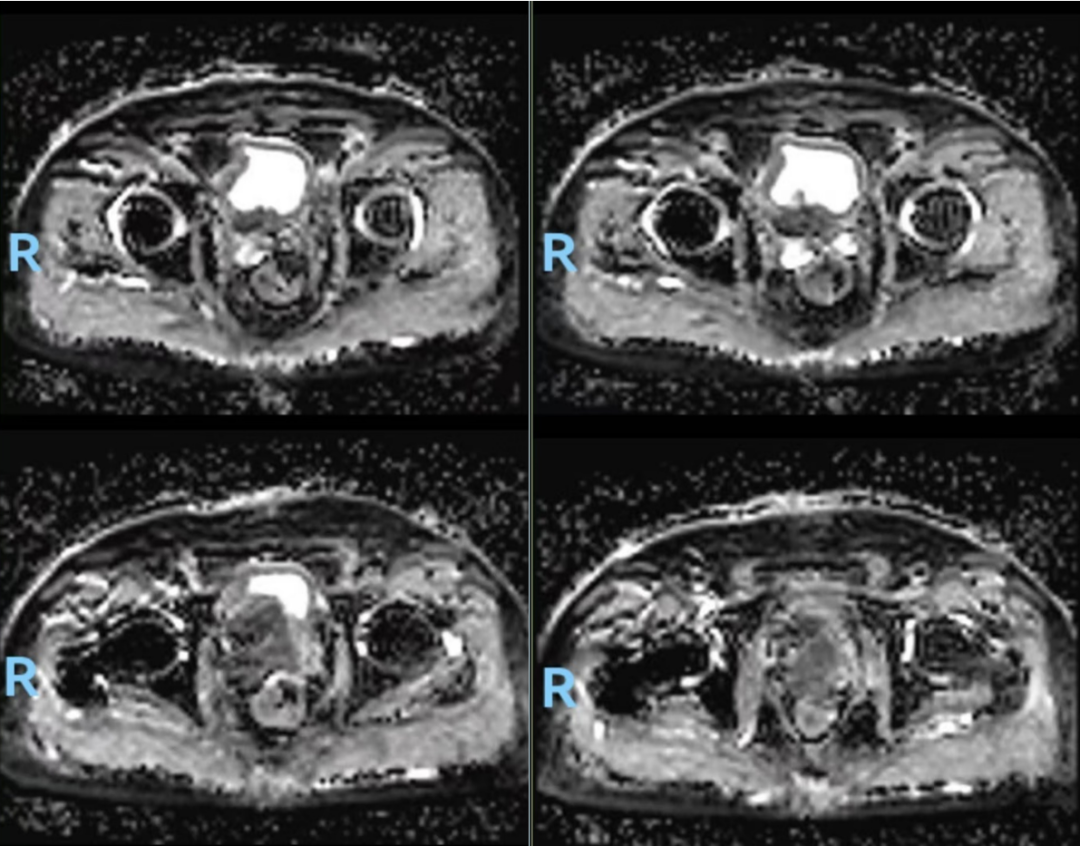

前列腺MR(图1,2024-04-18):1、考虑前列腺癌,PI-RADS 5,膀胱后壁、双侧精囊腺浸润;2、双侧耻骨及第1骶骨异常信号,转移瘤可能。

图1.前列腺MR(2024-04-18):前列腺体积不规则增大,约6.2cm(左右)x5.4cm(前后)x7.1cm(上下),中央带、外周带可见不规则片状短T2等T1信号灶,病灶向上突向膀胱,与膀胱后壁及精囊腺分界不清,DWI示病变呈弥散受限高信号,相应ADC信号减低。盆腔内见多个小淋巴结,较大者短径约为0.6cm。双侧耻骨及第1骶骨见稍长T1长T2信号,DWI弥散受限改变。直肠右侧壁局部增厚。诊断:1、考虑前列腺癌,PI-RADS 5,膀胱后壁、双侧精囊腺浸润;2、双侧耻骨及第1骶骨异常信号,转移瘤可能

图5.复查前列腺MR(2024-09-19):前列腺大小约4.2cmx3.5cmX3.5cm,以中央腺体增大为主,T1WI呈等信号,T2WI呈等、高信号,其中中央腺体前下份局部呈结节状突向膀胱颈,与膀胱后壁分界欠清,DWI扩散受限呈高信号,ADC图呈低信号:双侧外周带可见条片状低信号DWI未见明显高信号。双侧精囊腺大小和形态尚可,压脂像示局部信号减低膀胱精囊角对称。诊断:1、符合前列腺肿瘤治疗后改变2、右耻骨下支异常信号,考虑转移